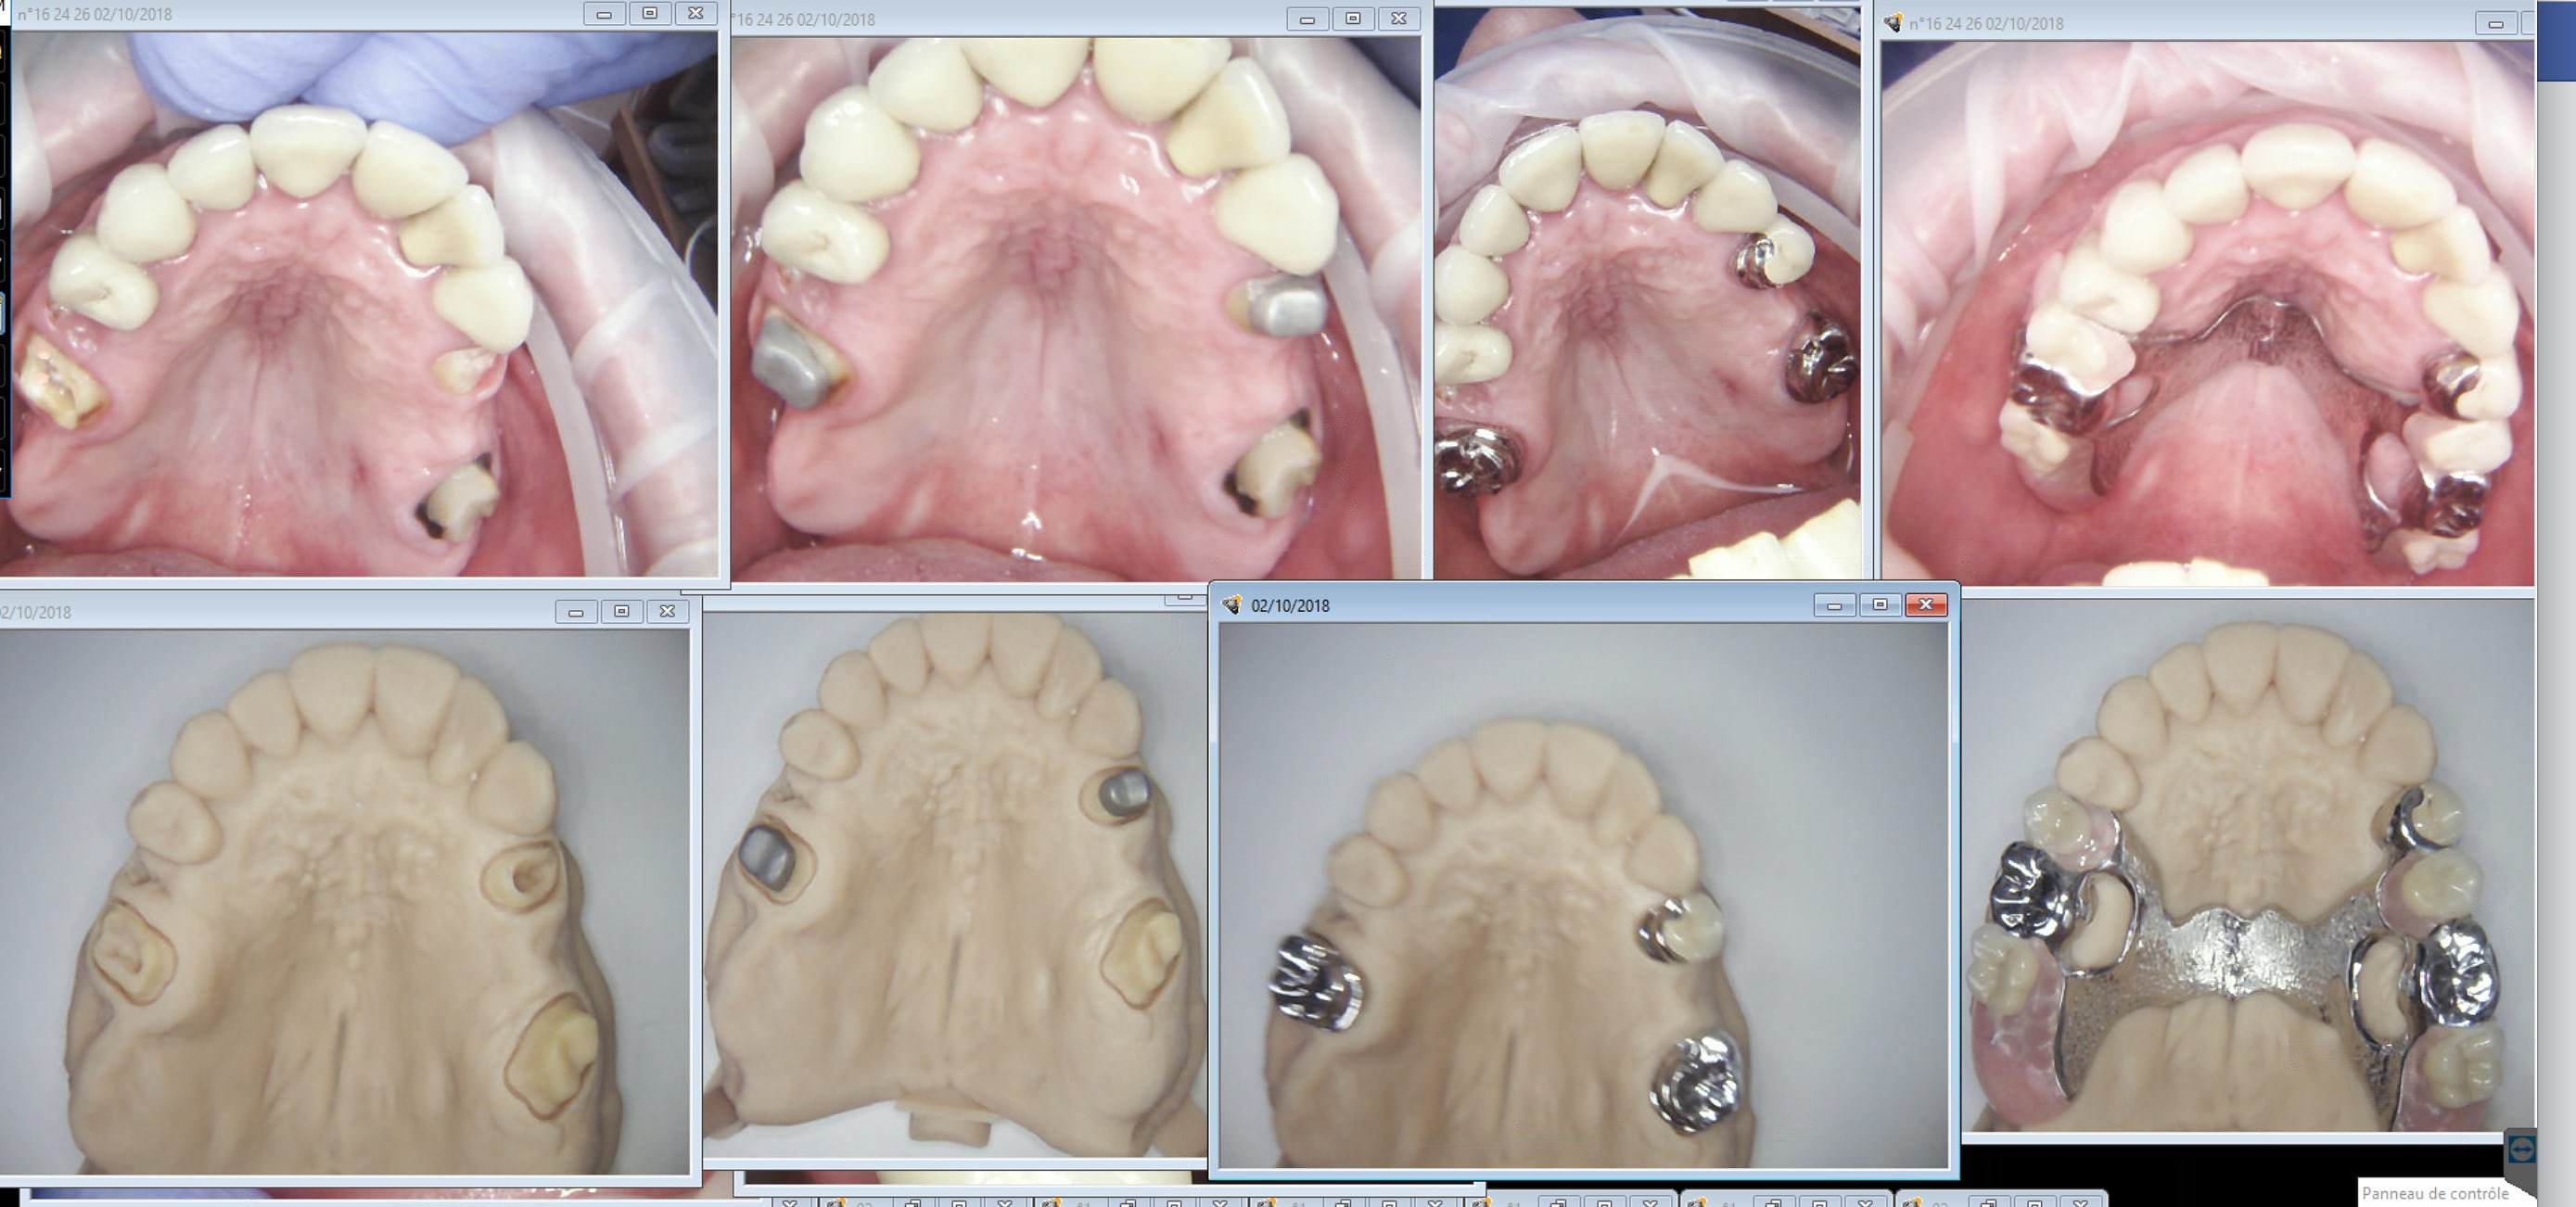

Junior, figures toi que je suis ravi de m'etre fait arnaquer par 3 shape qui vend sa trios hors de prix. Inlay core coiffes + stellites one shot. Continues à bien te faire chier avec tes silicones et tes alginates. -)))

Les empreintes.

Pour la plaque et les crochets tu as plusieurs propositions. Tu choisis. Plus de détails ? -)))